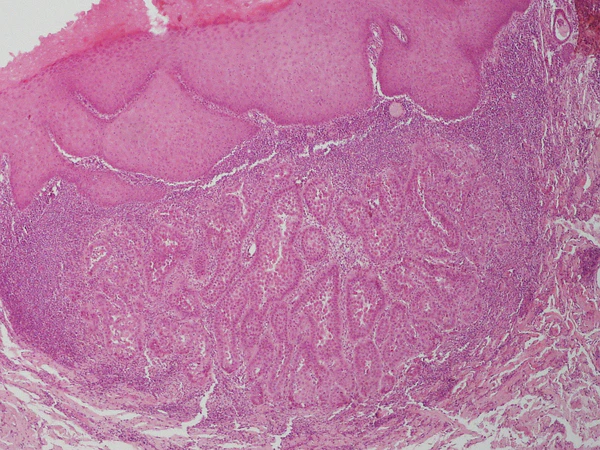

Гистологически выявляется чётко очерченное эпителиальное поражение доброкачественного характера, представленное пролиферацией плоского эпителия. В эпидермисе над опухолью отмечается дискератоз в виде небольших групп клеток, претерпевающих далеко зашедшую дистрофию и некробиоз. Клетки подвергаются акантолизу и представляются нередко в виде гомогенных, интенсивно окрашенных шаров. Подобные клетки идентичны клеткам в виде «зёрен», наблюдающимся при болезни Дарье. Под эпидермисом, образующим небольшие акантотические разрастания с выраженным гиперкератозом, располагается одна крупная или несколько мелких полостей, нередко щелевидной или неправильной формы. В просвете полостей определяется множество тонких ветвящихся сосочков, образованных рыхлой соединительнотканной стромой и выстланных одним слоем кубических эпителиальных клеток с гиперхромными ядрами. Полости с сосочками находятся в глубоких слоях дермы. В этих полостях определяется бледно окрашивающееся содержимое, в котором встречаются слущенные эпителиальные клетки с пикнотичными ядрами. В глубоких отделах опухоли обнаруживаются железистые образования или солидные комплексы, состоящие из более крупных клеток с базофильной цитоплазмой и тёмно окрашивающимися ядрами[1].